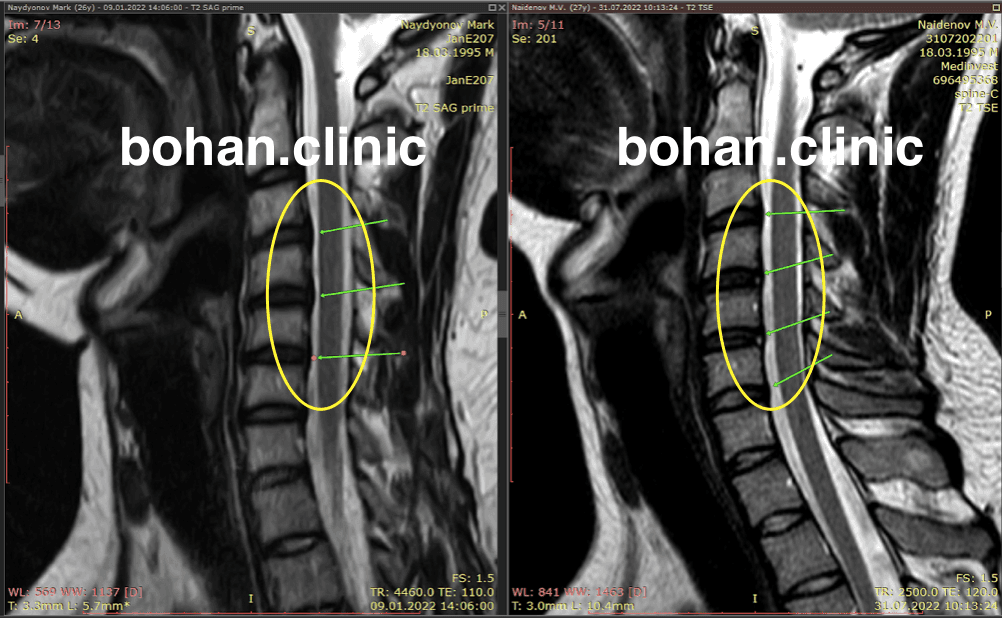

Метод лікування грижі шляхом стимуляції резорбції в Україні був впроваджений у 2020-2021 роках.  Алгоритм оцінки грижі на предмет резорбції, що використовується у клініках – є авторським, розроблений лікарем Боханом А.Ю.